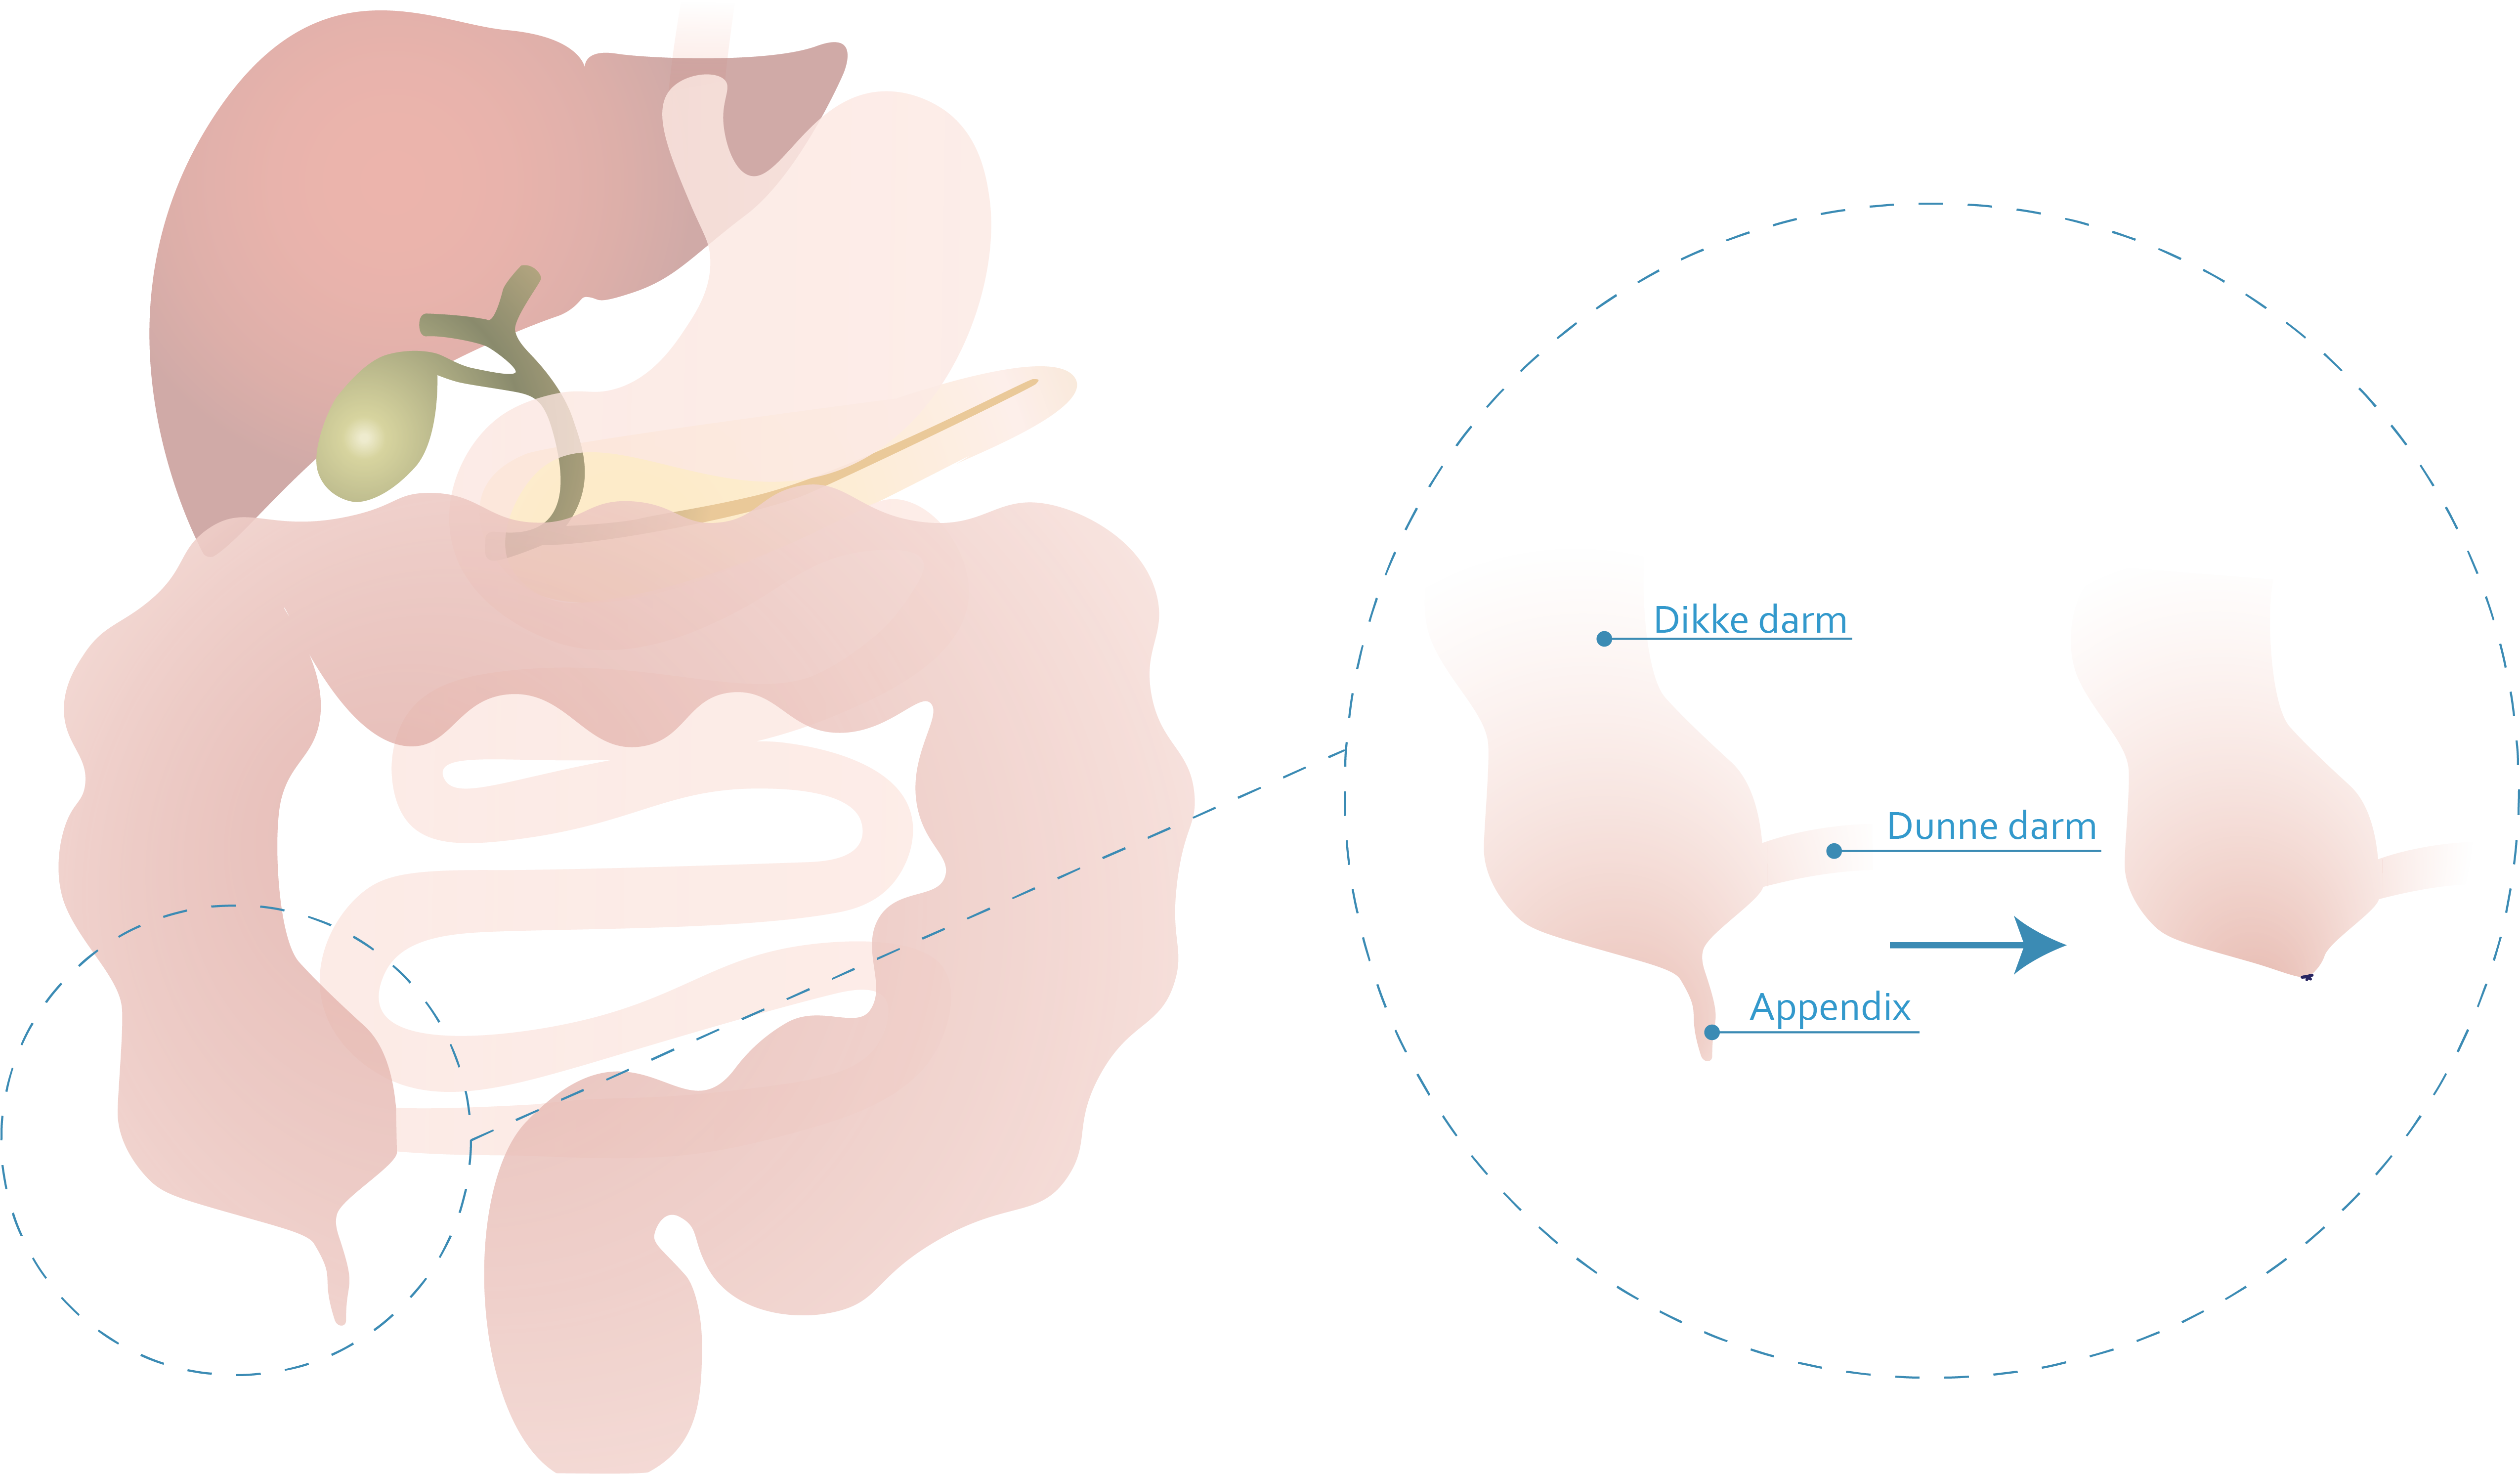

De appendix is een klein, wormvormig orgaan aan het begin van de dikke darm, gelegen rechts onder in de buik. Hoewel het geen duidelijke functie lijkt te hebben, speelt het mogelijk een rol in het immuunsysteem.

Bij een appendectomie wordt de slagader naar de appendix doorgenomen en wordt de basis van de appendix ter hoogte van blinde darm (caecum) onderbonden. Soms dient de inplanting van de appendix ter hoogte van het begin van de dikke darm mee weggenomen te worden (caecumbodemresectie).